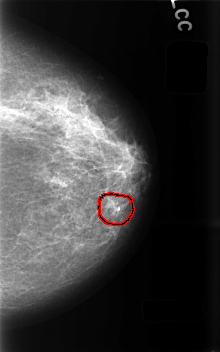

C_0487_1.LEFT_CC

LEFT_CC LINES 4568 PIXELS_PER_LINE 2856 BITS_PER_PIXEL 12 RESOLUTION 50 OVERLAY

FILE: C_0487_1.LEFT_CC.OVERLAY

TOTAL_ABNORMALITIES 1

ABNORMALITY 1

LESION_TYPE CALCIFICATION TYPE PLEOMORPHIC DISTRIBUTION CLUSTERED

ASSESSMENT 3

SUBTLETY 4

PATHOLOGY BENIGN

TOTAL_OUTLINES 1

BOUNDARY